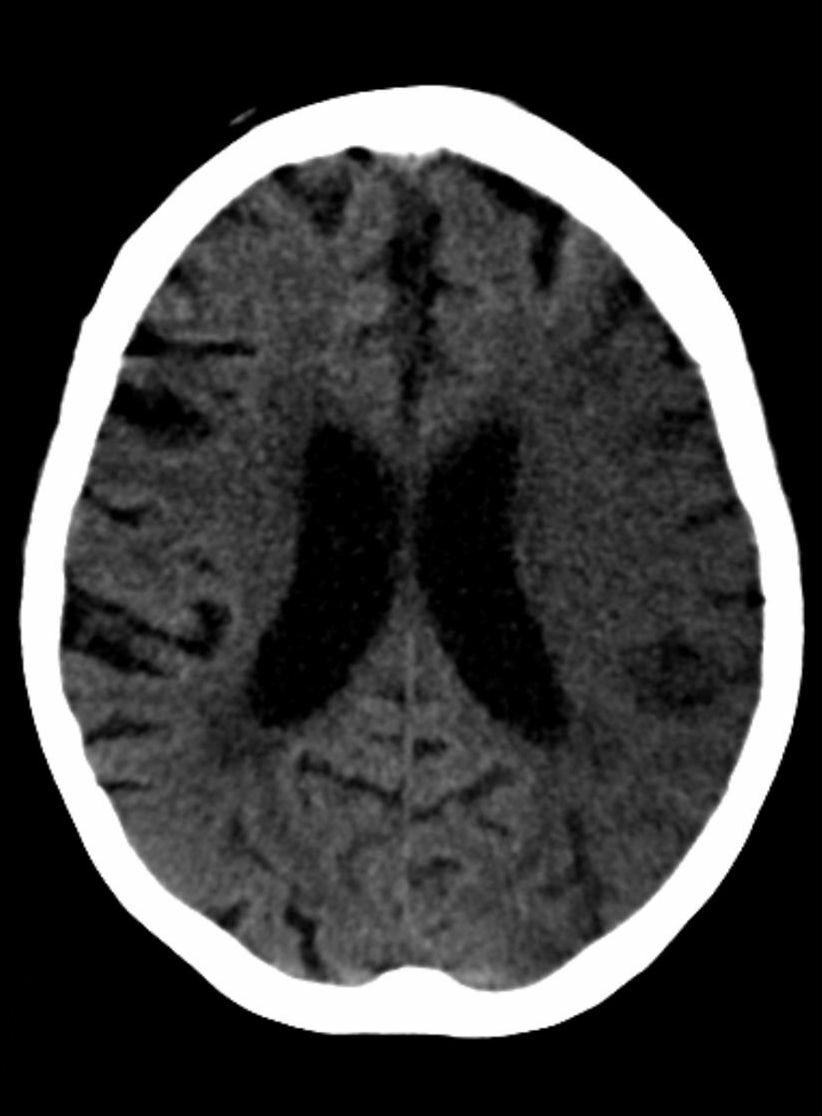

what does this CT scan show?

A

hypodense ischaemic stroke